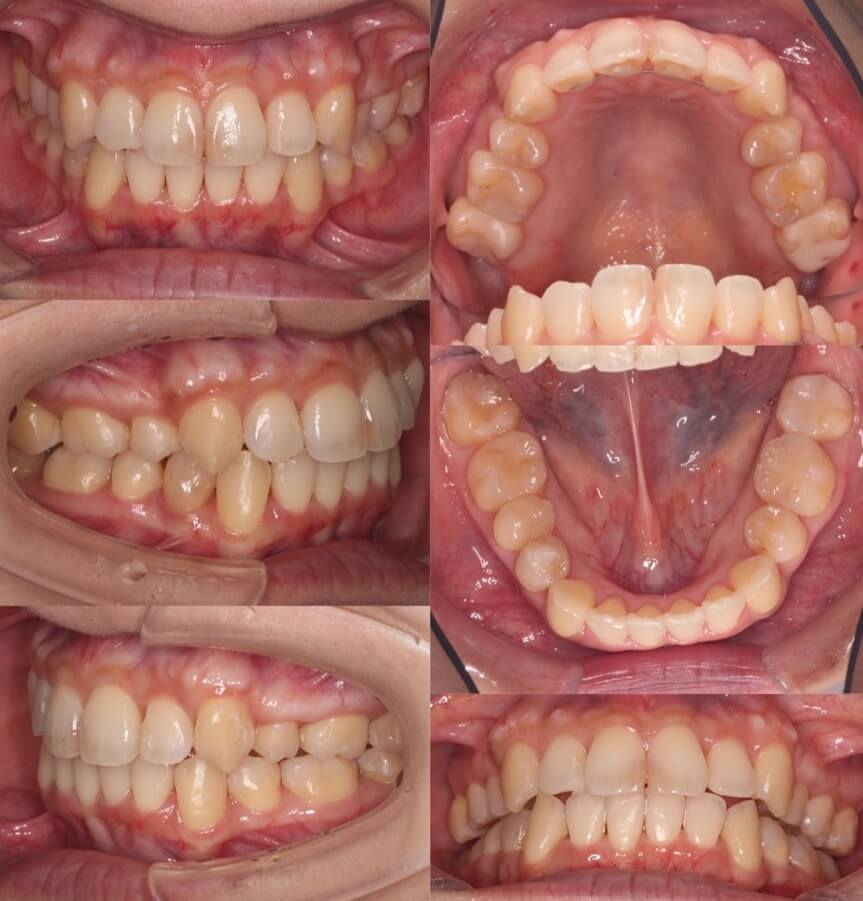

63歳女性・反対咬合・マウスピース装置

<症例概要>

主訴:前歯のかみ合わせ

年齢・性別:60代女性

住まい:千葉県八千代市

症状:反対咬合・叢生

治療方針:上顎前歯前方拡大・下顎後方移動

治療装置:マウスピース型矯正装置(アライナー装置)

治療期間:3年2か月

アライナー枚数:60+35-22ステージ

リテーナー:上下フィックスタイプ+プレートタイプ

治療費用:990,000(税込)

代表的副作用:痛み・治療後の後戻り・歯根吸収・歯髄壊死・歯肉退縮

▶︎その他の副作用

【治療シミュレーション】

下の歯並びをIPRを加えながら後方移動させています。上の前歯は歯茎が下がらない程度で前方移動させています。

年齢的なことを配慮して、できる限り歯の移動量は最小限にしています。前歯のかみ合わせは奥歯を守るために重要な役割を果たします。